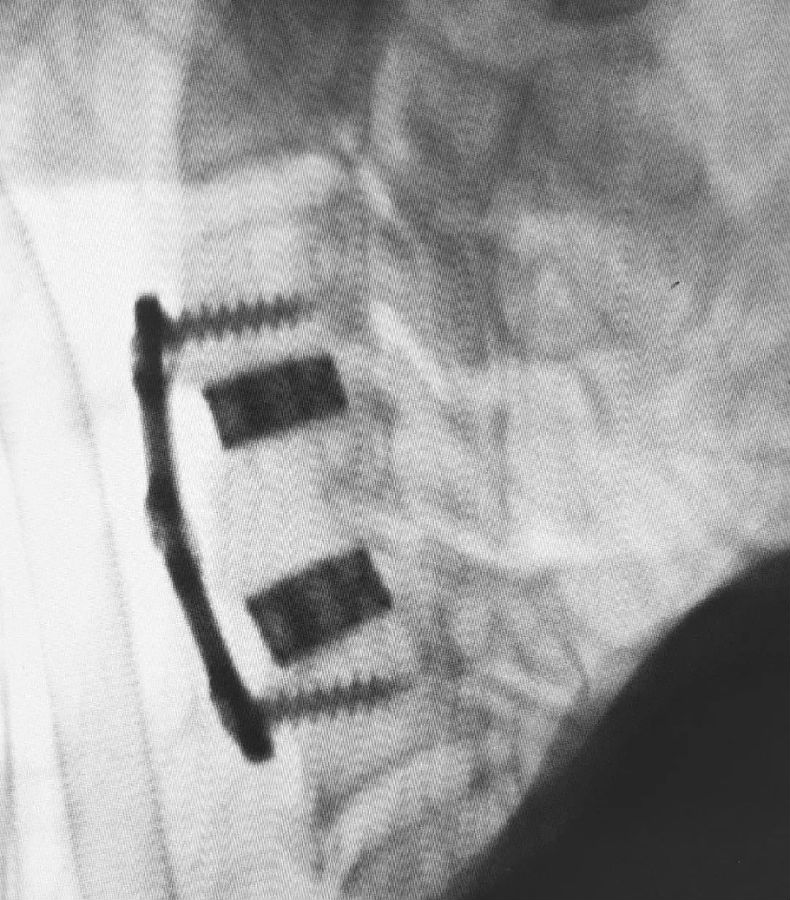

经过完善的术前准备,李玉伟教授及其团队为张大爷顺利实施了手术。用时不到1个小时,切口只有两个横指宽,出血不到30ml。

“术中透视显示3D打印融合器与椎体紧密贴合”